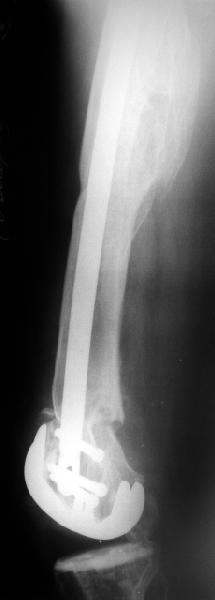

В итоге сделали антеградный остеосинтез. В дистракторе свежий перелом вправился сразу, а вот старый - оставил проблему, дистальный отлмомк остался все равно кзади. И гвоздь бы прошел кпереди от него, а ретроградный - перфорировал бы передний кортекс. Так что пришлось еще сделать чрескожную остеотомию через перелом, чтобы малость мобилизовать дистальный отломок. Снимки в прилжении.

Критика, комментарии, мнения?

The radiographs look excellent and a good outcome would be anticipated. The idea to osteotomize the femur shaft to compensate for the prior shaft malunion was clever and should work fine.

I can't actually see the osteotomy on either radiograph. Is it more proximal than we see in these radiographs or so well aligned as to be not visible?

Отправитель: Alexander Chelnokov 02 Июнь 2004, 13:58

TAC> idea to osteotomize the femur shaft to compensate for the prior shaft malunion

TAC> was clever and should work fine.

The "idea" was an emergency appeared when the nail tip proceeded to the fracture level and became targeting anteriorly to the distal fragment.

TAC> I can't actually see the osteotomy on either radiograph. Is it more proximal

TAC> than we see in these radiographs or so well aligned as to be not visible?

The osteotomy was perfromed trough the fracture site. See the image.